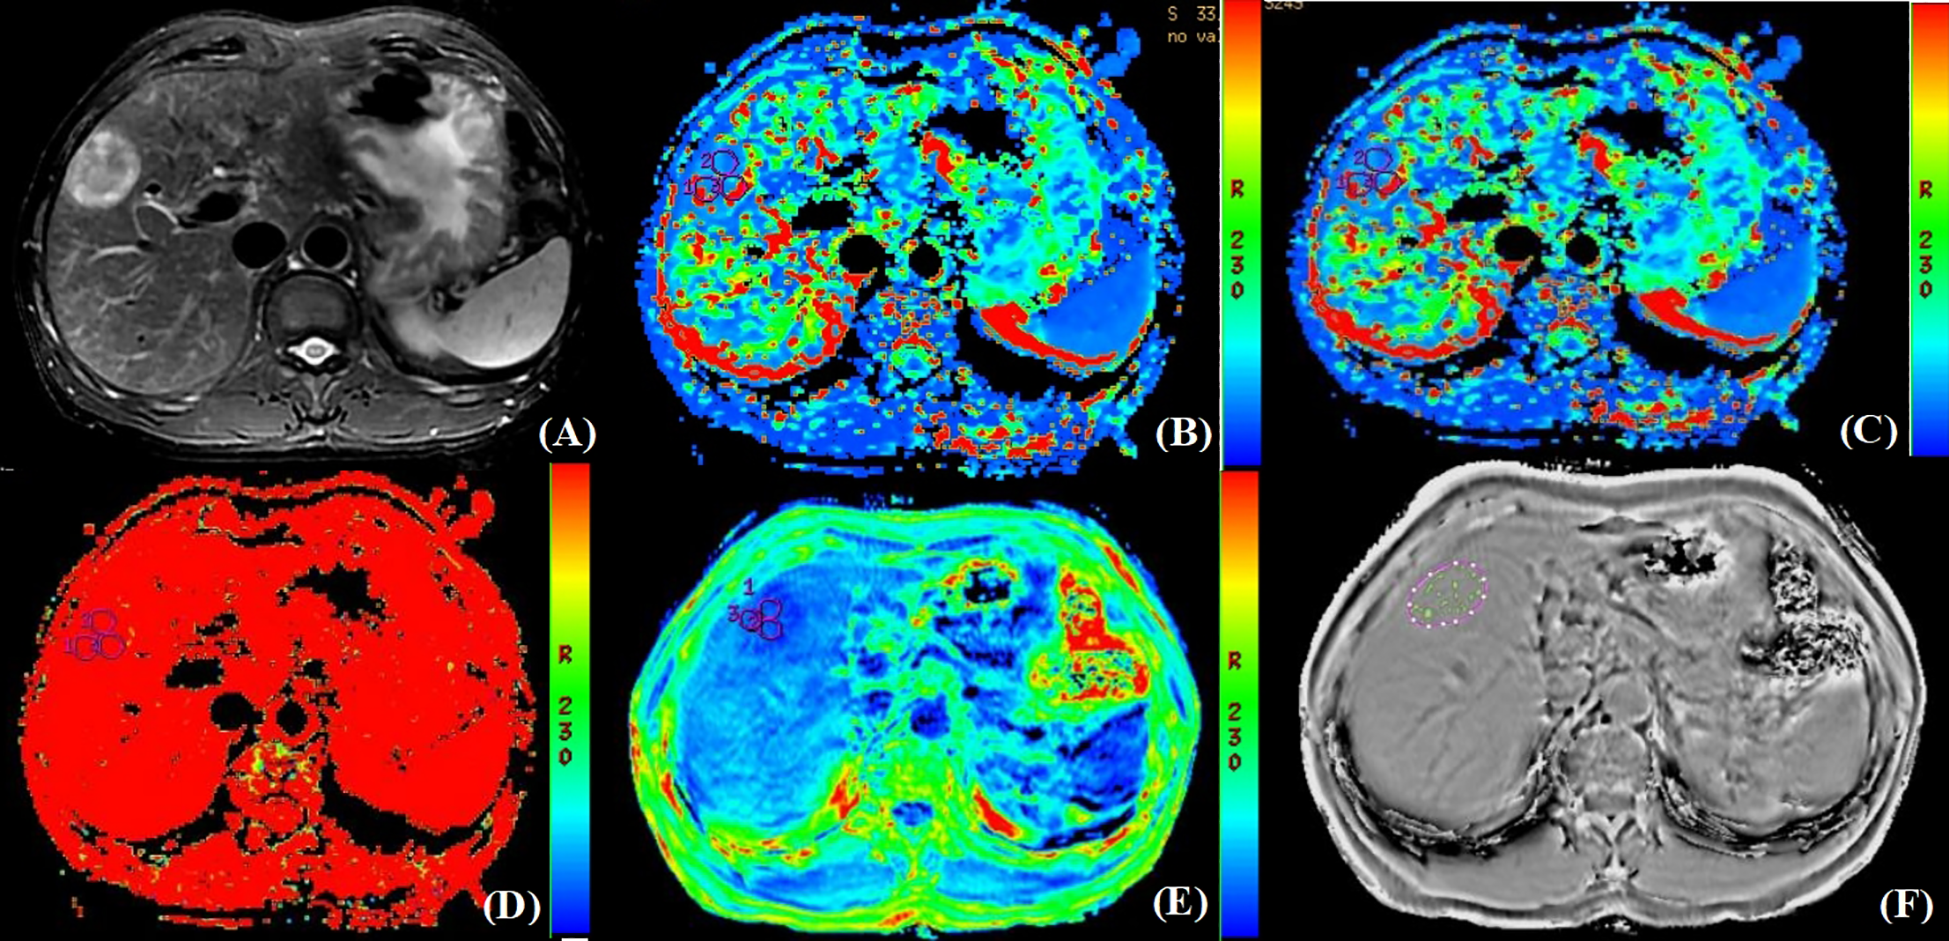

Figure 2

Pathologically confirmed HCC with MVI in a 66-year-old male. (A) T2W image. The circular lesion in the hepatic right lobe presented with a slightly high signal intensity and a clear boundary. (B–E) Parametric maps (D, D*, f, and R2*, respectively). The calculated average values of D, D*, f, and R2* for the drawn ROIs were 0.402×103mm2/s, 0.032mm2/s, 0.435×100%, and 45.482Hz, respectively. (F) The ROIs were delineated along the tumor edge and the ITSS-ratio was automatically calculated which showed as the green area within the tumor. The ITSS-ratio was 0.200.

As shown in Table 5, there were statistically significant differences in D (P<0.001), D* (P=0.003), R2* (P<0.001), and ITSS (P=0.025) between MVI-positive and MVI-negative groups. The D and D* values of MVI-negative group were significantly higher than those of MVI-positive group, which in MVI-negative group were 0.892×10-3 (0.760×10-3, 1.303×10-3) mm2/s and 0.055 (0.025, 0.100) mm2/s, and in MVI-positive group were 0.591×10-3 (0.372×10-3, 0.824×10-3) mm2/s and 0.028 (0.006, 0.050) mm2/s, respectively. The R2* and ITSS values of MVI-negative group were significantly lower than those of MVI-positive group, which in MVI-negative group were 29.290 (23.117, 35.228) Hz and 0.146 (0.086, 0.236), and in MVI-positive group were 43.696 (34.914, 58.083) Hz and 0.199 (0.155, 0.245), respectively. No statistical significance was observed for f (P=0.239) value in those patients with MVI-positive group compared with MVI-negative group (Figures 2, 3).